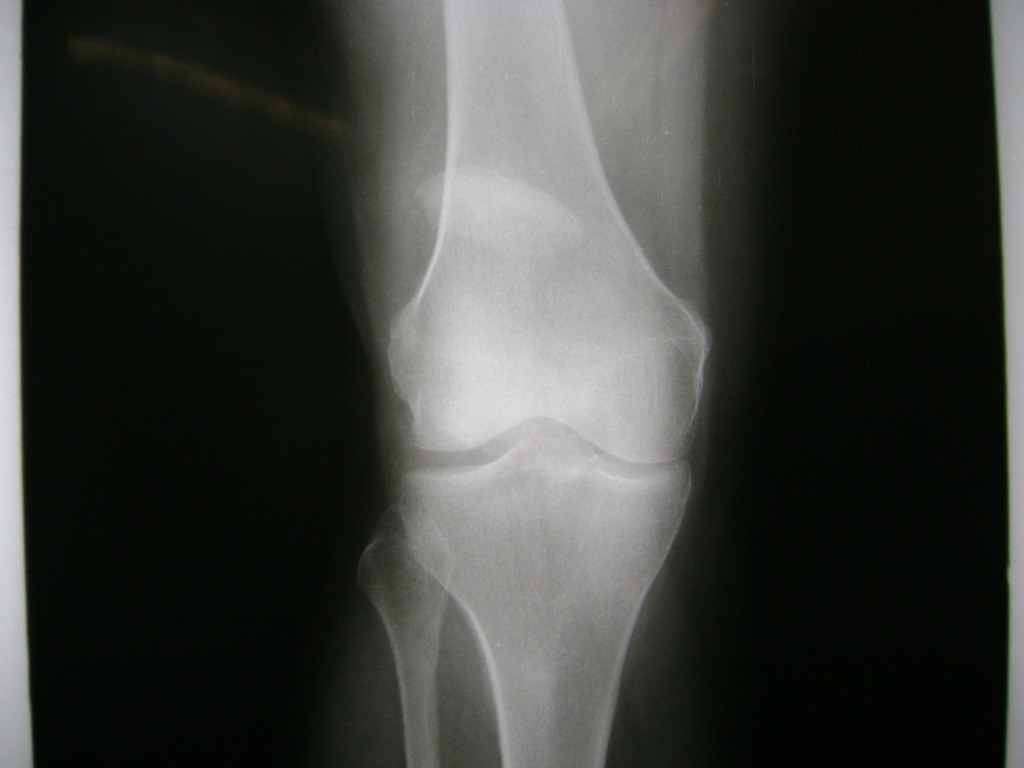

Cirugías de Calcaneo - Rodilla

La artroscopia de rodilla es un cirugía en el cual la estructura interna de la articulación es examinada ya sea para realizar un diagnostico o para realizar un tratamiento, este procedimiento se realiza utilizando un instrumento parecido a un pequeño tubo llamado artroscopio.